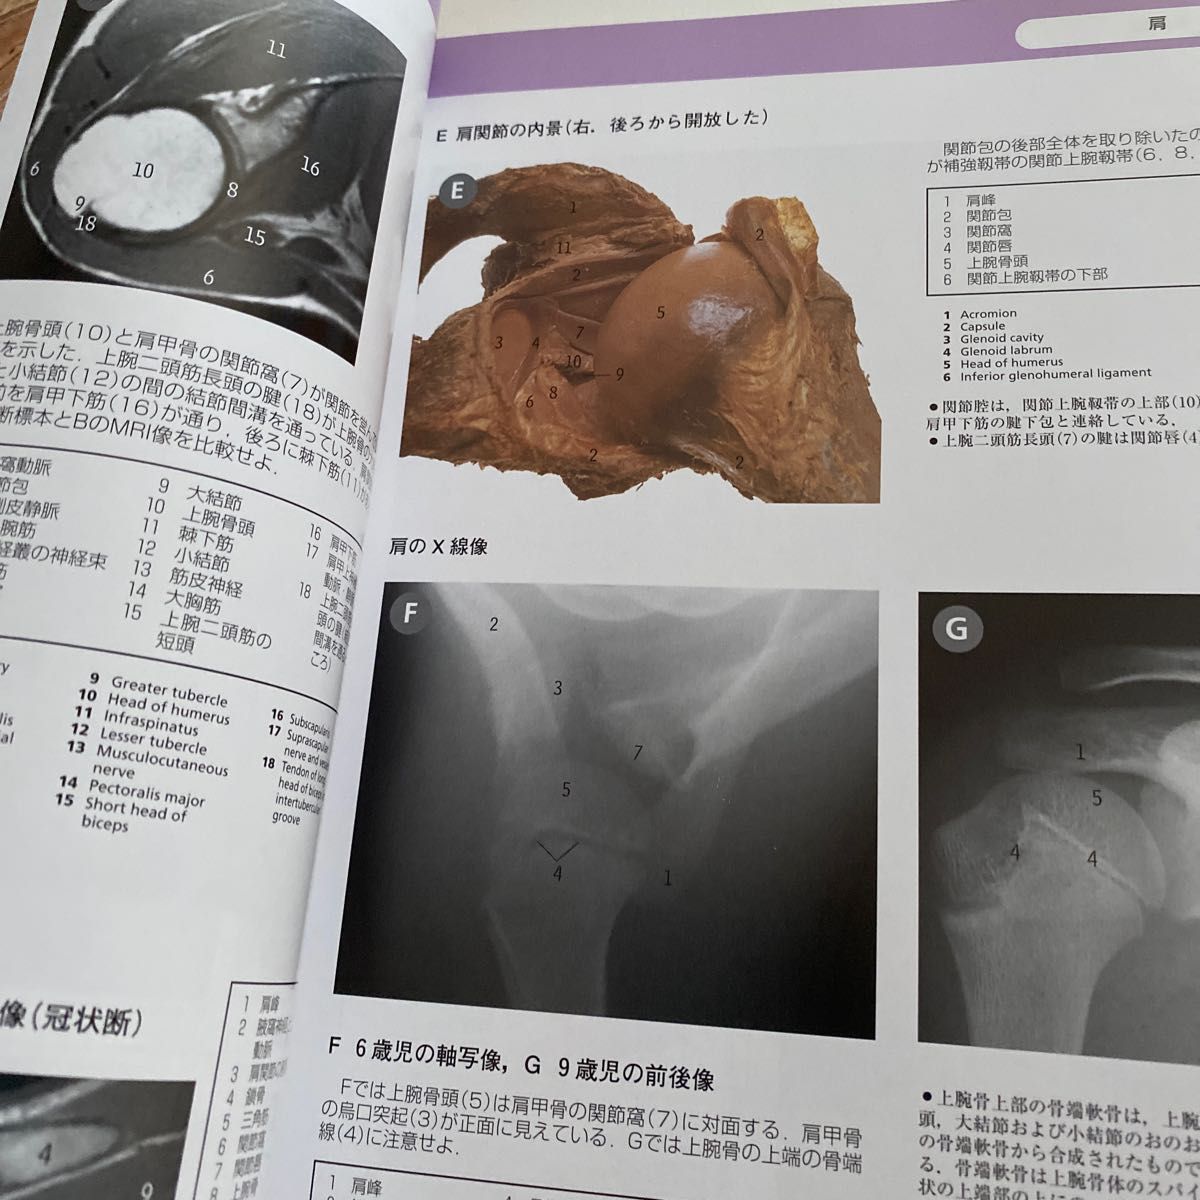

NEW!頭部から胸部の解剖 | 京都科学, CT・MRI画像解剖ポケットアトラス 第4版 2巻 胸部・心臓・腹部,